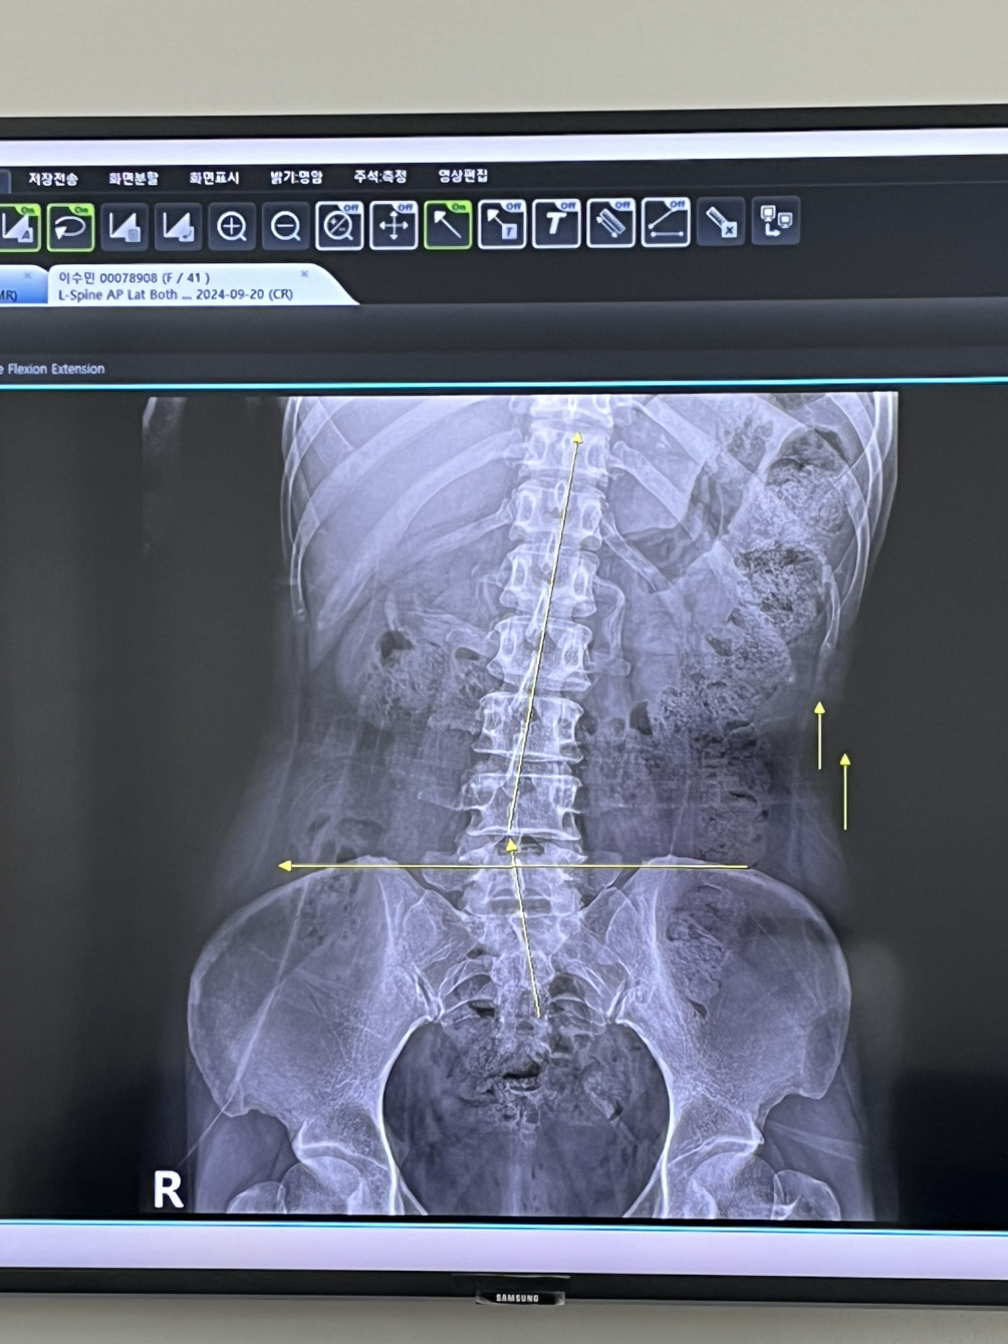

우울증과 함께 온건 디스크파열이었고 수술을 했다. 그 과정에서 막힌 경혈들을 뚫느라 수기마사지를 받으러 다녔고 2년이 지금도 그때 틀어진 골반을 맞추느라 일주일에 서너 번 재활운동을 하고 있다.